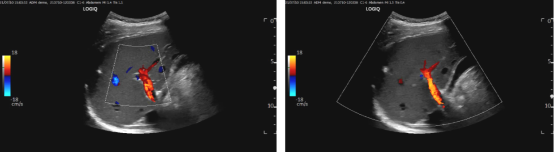

) y: M$ s9 m/ z) e6 F 彩色多普勒取样

4 S: W- n! R( M$ j" r6 M; t CDI用于ROI内沿着一系列扫描线的多个取样容量的多普勒技术。它是与2D图像相结合,并受2D增益影响。CDI取样可展示:时间、相对速度、方向和湍流的出现。为更好的展示彩色血流数据,应使数据最优化,包括ROI的大小,2D扇区大小,彩色阈值和速度标尺。

3 ^# Z* @& V0 H3 `, y- b6 h4 g( C 1 / h& K9 H( L3 f* ~* `

ROI和2D扇区大小

. C5 q5 Z, X( o% W# i6 E1 f+ P 在使用CDI前,应先确定取样框区域,调整2D扇形大小至最小深度和宽度。可以使彩色帧频达到最优。预设置变焦模式是2D展示的最佳替代,确定CDI检测区域的大小和位置。ROI应包括所有要评估的血流信息。将ROI调整到尽可能窄和浅,可使帧频和速度标尺最大化,以取得最佳瞬时分辨率和血流速度分辨率。

^; u+ b4 a8 D, {3 U 2

+ [* v$ @; [& I: X' ?& s9 | 彩色增益(Gain) / ~" F: G* a3 G1 e6 v& G' D5 ]) P1 w$ F

彩色增益应通过以下方式来调整:缓慢调高直到任意的彩色血流染斑高于ROI的边缘,随后缓慢调低直至染斑消失。在检测中,彩色增益应被频繁调节,因为始终保持过低的彩色增益,声波传输时的变化和信号衰减可能会误判为血流不足。 2 x& @- h' w7 w- A" N$ R- z

在灰阶图和PW中,也可通过调整彩色增益来展示解剖结构中的“最佳”血流。通过调节可使灰阶图中无法清晰识别的结构有效填充,以确认结构的存在。 2 }4 T) I& h n! C2 a% k

3

4 Y; E) t: H l/ Z" V, w$ j+ z 彩色阈值(Threshold/Balance/Write Priority) # F2 Y6 }/ l% @5 I

最基本的色彩图展示了血流的方向:阈值为零时通常显示为无色彩,CDI取样中,朝向探头的血流设置为红色,反之则为蓝色。每个方向的速度标尺代表了取样频率和探头的奈奎斯特极限,心脏预设通常速度标尺设置为50~70 cm/s。通过色调或亮度区分不同血流速度:深色代表低速,而亮色代表高速(例如:从深红色到亮黄色)。层流使用一种纯粹的颜色,而湍流则使用多种颜色的拼接。操作者还可以选择个性化设置,如在色彩图中增加绿色和黄色,以作为区分湍流和层流的替代方法,突出血流速度的变化。 - Y3 [1 d; H; G2 W

4 6 n& q: {2 p4 K. n& Q% j

彩色速度标尺(Scale/PRF) * {7 N7 |) n! U- d1 u* _' O1 ]

彩色速度标尺的最优化至关重要,其奈奎斯特极限通常应被设置为50~70 cm/s。代表了平均速度标尺。将其设为高速度标尺时,可展示一些没有混淆现象的彩色血流数据(如:层流)。奈奎斯特极限作为默认设置,对于瓣膜返流喷射的展示尤为重要。所展示的返流速受几个变量影响,其中一个是奈奎斯特极限,较低的比例设置在相同返流量呈现出的大小与高比例设置要大得多。一致的设置可以加强对于慢性瓣膜病患者纵向研究的可重复性。另外血压也会相应的影响返流口喷射大小的展示。

Y$ z- G; ^; s 当取样框中所有的血流都处于低速时(如心房内或肺部),会展示为几乎没有颜色的多普勒信号,因为大部分速度属于靠近基线的“黑色”低速波段。将奈奎斯极限设置为30 cm/s左右是低血流表现状态的一个好的起始点,系统会用更明亮的色调展示更低的速度。 : Q+ N q, @& R5 l

一些超声系统会提供自动最优化功能,可以帮助迅速获取最佳的CDI图像。操作者应了解并更好地使用这个功能。